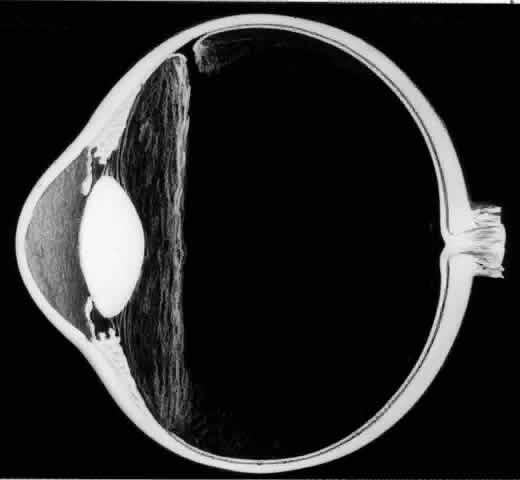

The outer surface of the inverted retinal flap (Fig. 1) should be examined for signs of epiretinal tissue proliferation, which may produce radial or star-shaped folds in the flap. Vitreous base traction produces detachment of the anterior edge of the giant tear and the pars plana epithelium anterior to it in 82% of giant retinal tears.9 It is important to identify and treat detachment of the pars plana epithelium that extends beyond the ends of the giant tear because leakage of subretinal fluid beneath it can be a potential source of postoperative posterior retinal detachment.

Fig. 1. Superior giant retinal tear extending from 9:30 to 3:30 meridian. The retina is torn at the posterior border of the vitreous base. Posterior retinal flap is invertd over the optic disc. Anterior edges of giant tear, ora serrata, and pars plana are detached from the 9:30 to 3:00 meridians as a result of vitreous base traction.